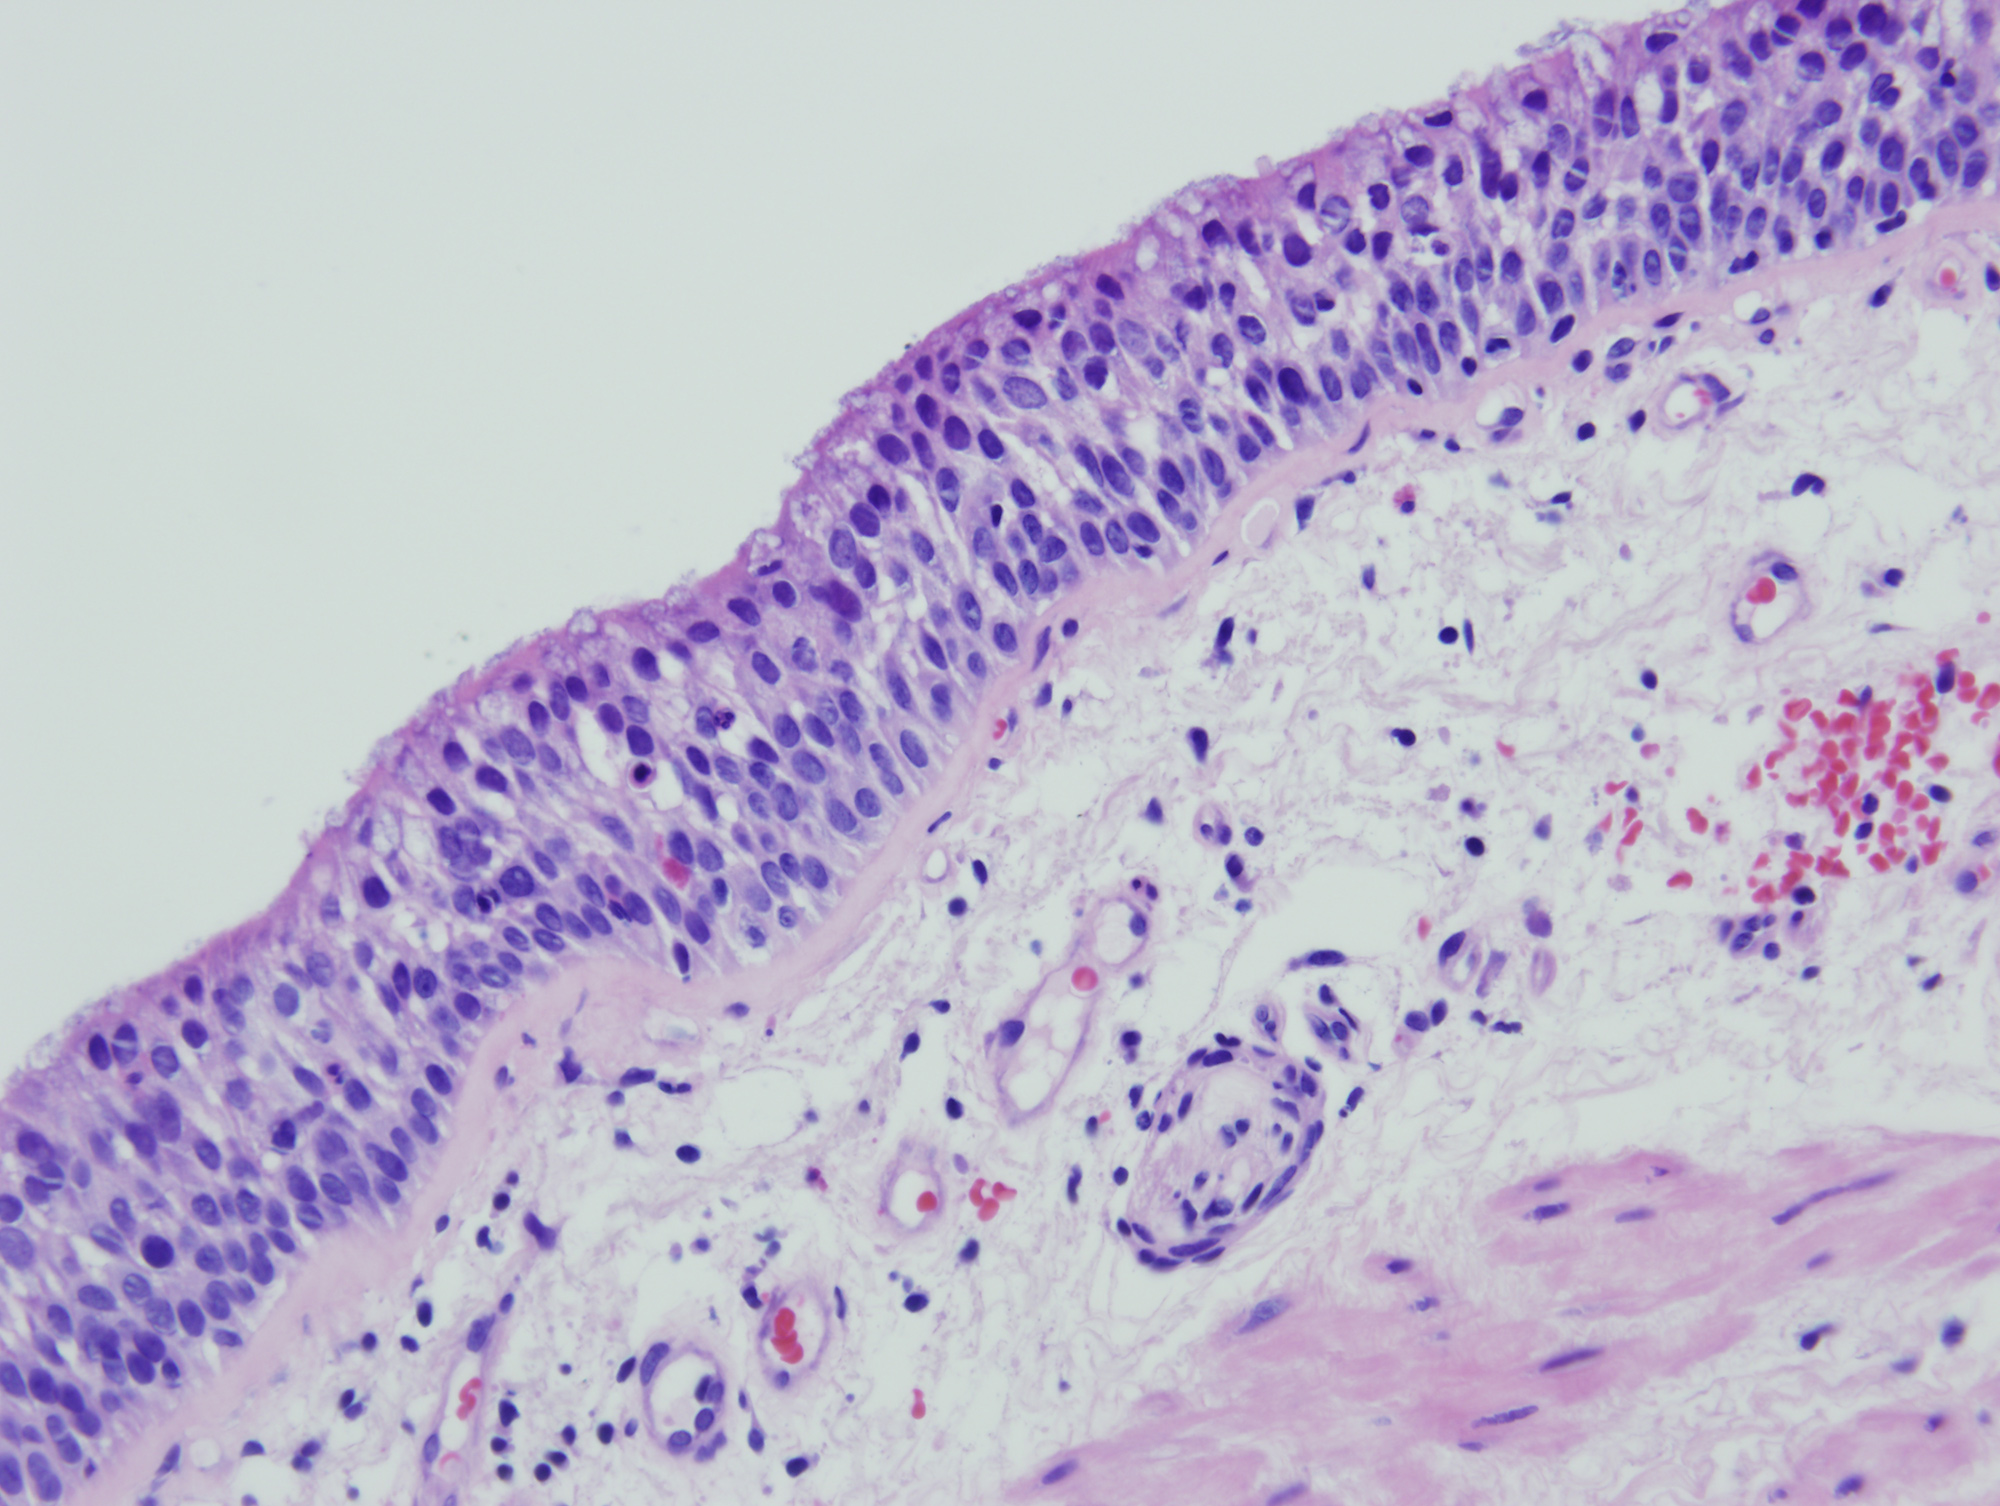

In the years to come, the NCI plans to incorporate image-recognition technology to help archive images of cancer specimens from the EDRN. Then, much like how computer algorithms comb through images of star clusters,these images could be analyzed for early signs of cancer based on a patient's age, ethnic background and other demographics, Crichton said in the statement.

Credit: Early Research Detection Network/University of Colorado